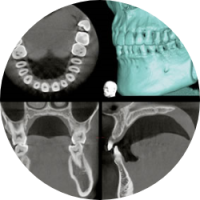

適切な検査と正確な診断

歯や歯ぐきの中は直接見ることができないので、レントゲン診査が必要になります。当院のレントゲンはデジタルCTを用いておりますので、放射線の量が非常に小さい、身体に優しいレントゲンです。また 3次元的に解析することで診断能力は格段に向上しました。